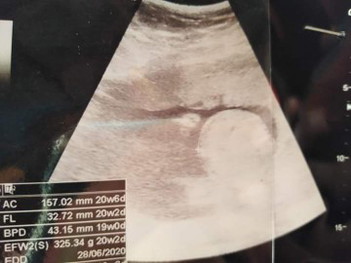

นี่มันส่วนหัวน้องค่ะ ดูเพศไม่ได้ หมอไม่บอกเพศหรอคะ